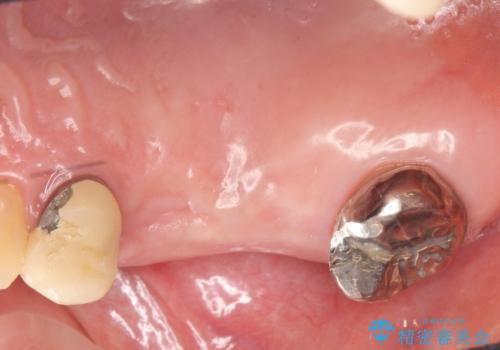

右上の567ブリッジを外したところ、右上5は歯根破折により保存不可能だったため、右上56部にインプラントを埋入し欠損補綴を行いました。

今回用いたオールセラミッククラウンはジルコニアフレームという白い素材の上にセラミックを盛っているため、審美性が非常に高いのが特徴です。

また、ジルコニアは人工ダイヤモンドの材料にも使われているほど高い強度を持っており、そのためオールセラミッククラウンは審美性だけでなく、奥歯やブリッジの補綴も可能とするクラウンです。